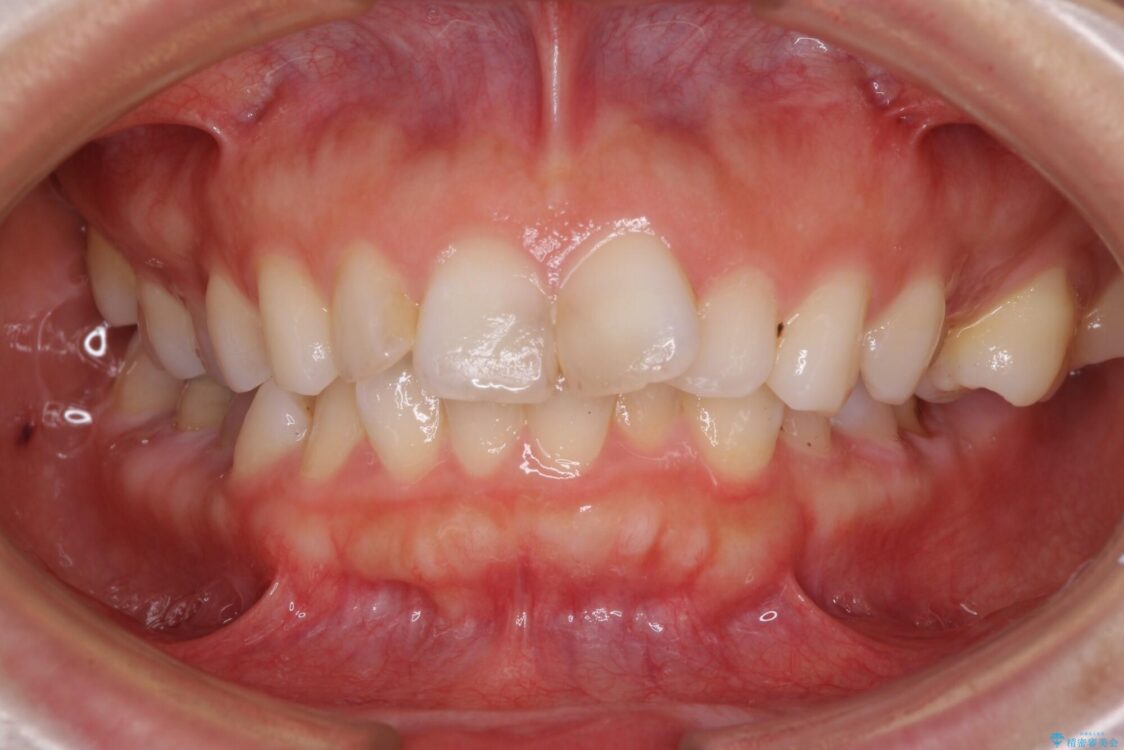

口元の閉じにくさと、奥歯の咬み合わせを気にして来院された患者様です。

左下の大臼歯2本が顕著に舌側に傾斜しているため、まずは奥歯の咬み合わせを改善をし、その後上下左右の第1小臼歯4本を抜歯することで口元を引っ込めながら整えることとしました。

治療前

• 【モニター】出っ歯と咬み合わせを改善 ワイヤー装置の抜歯矯正 治療前画像